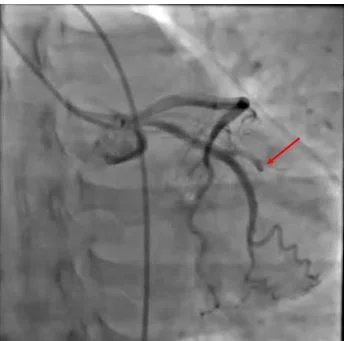

Post angioplasty with good flow in OM1